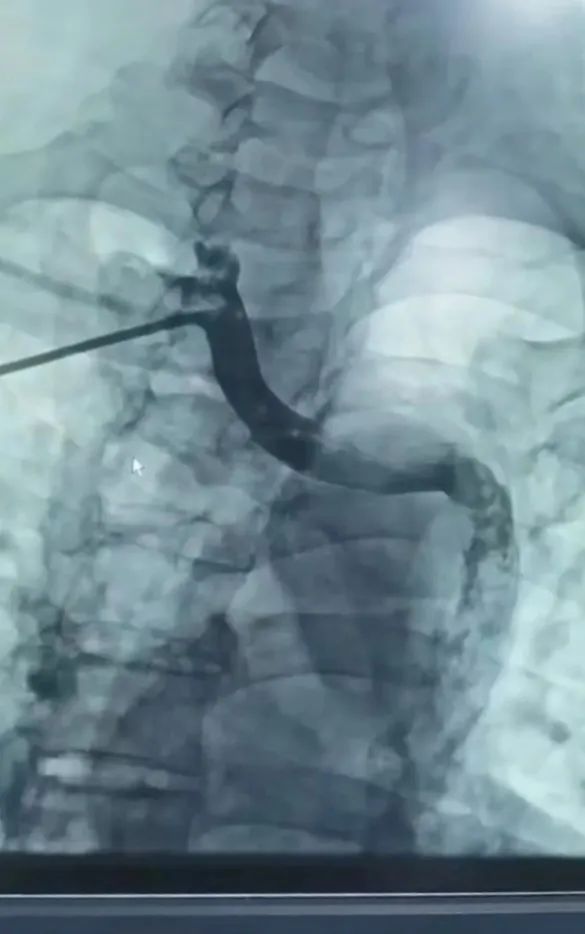

先天性永存左上腔靜脈(DSA)

Micra無導線起搏器植入術后(DSA)